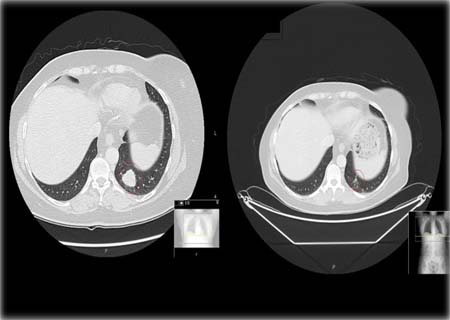

Foto: Royal Marsden / tumor de paciente reduz após tratamento de 12 semanas

“Em imunoterapias, nós nunca tínhamos visto taxas de redução do tumor com mais de 50 por cento, de modo que (isso) é muito significativo”, disse ao The Telegraph.